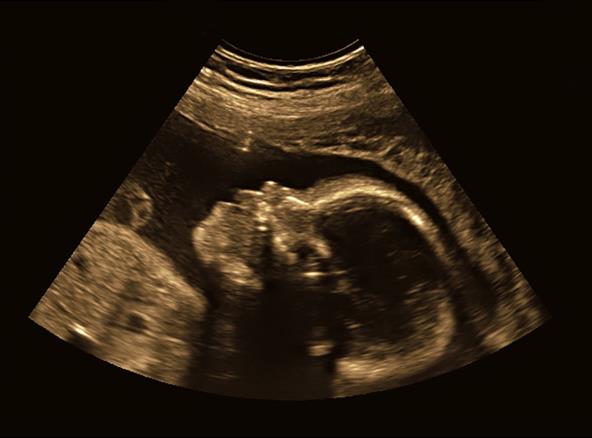

Tokom trudnoće doktor i mama su na ultrazvuku primetili da beba ima isplažen jezik, mislili su da je to slatko i simpatično, a onda je sa rođenjem deteta potvrđena dijagnoza retke bolesti.

"Uvek sam mislila da je slatko što je isplazio jezik na tim snimcima sa ultrazvuka. U realnosti bila je to makroglosija uzrokovana BVS-om. Malo doktora je upoznato sa ovim sindromom, pa su čak i oni mislili da je simpatično, a ja sam i na društvenim mrežama ispričala koliko je sladak", ispričala je gospođa Rot, kojoj je Bejker četvrto dete, prenosi Mirror.